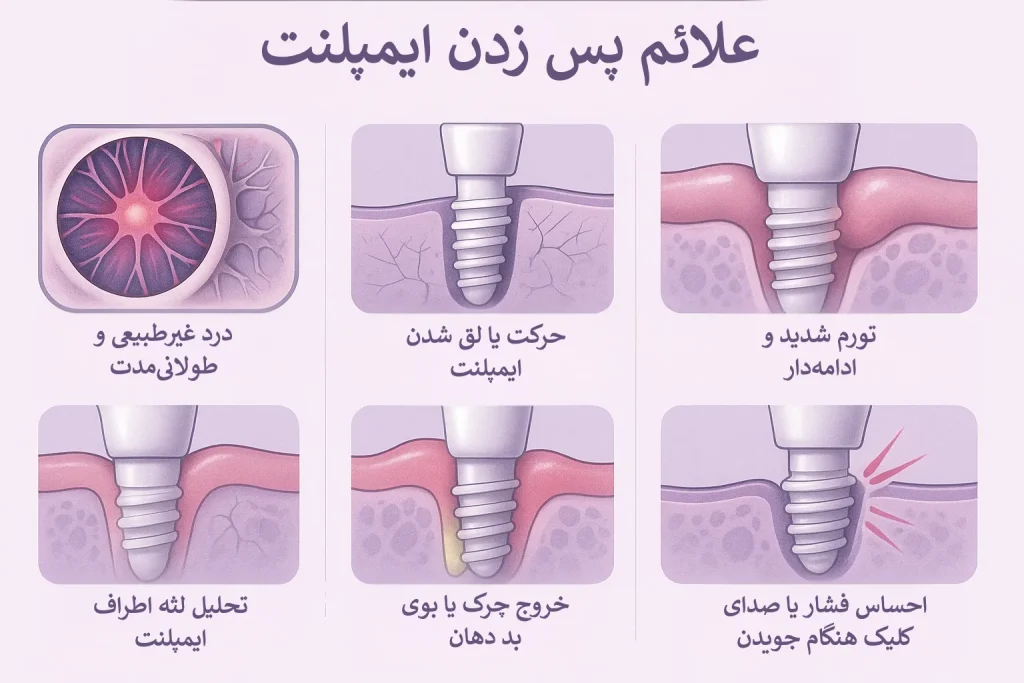

علائم پس زدن ایمپلنت

کارآمدترین روشی که میتوان به وجود یک عارضه پی برد، بررسی علائم بالینی آن است. در واقع، زودتر از هر آزمایش و هر نوع بررسی تخصصی، تشخیص علائم بالینی است که به کمک ما برای تشخیص زودهنگام میآیند. علائمی مانند درد غیرطبیعی و طولانیمدت، لقی ایمپلنت یا حرکت درجای آن یا تحلیل لثه و تورم ادامهدار، از علائم پس زدن ایمپلنت است. در ادامه به بررسی ویژگیهای هر کدام از این علائم خواهیم پرداخت.

۱. درد غیرطبیعی و طولانیمدت

درد خفیف بعد از ایمپلنت، طبیعی است؛ اما در صورتی که درد بعد از کاشت ایمپلنت، با علائم زیر همراه شود، پس از حالت طبیعی خارج شده و میتواند علت پس زدن ایمپلنت به حساب بیاید.

- در صورتی که درد، بیش از یک هفته ادامه پیدا کند.

- درد با روند افزایشی همراه باشد.

- درد به حالت ضربانی و تیر کشیدن باشد.

۲. حرکت یا لق شدن ایمپلنت

این نکته را در نظر داشته باشیم که ایمپلنت سالم، هیچ وقت در جای خود تکان نمیخورد. بنابراین هر نوع حرکت و لق شدن ایمپلنت میتواند به معنای پس زدن ایمپلنت باشد. لق شدن ایمپلنت میتواند نشانه مشکلات زیر باشد.

- وجود عفونت در ایمپلنت

- ادغام استخوان فک با ایمپلنت به خوبی انجام نشده است.

- شل شدن روکش یا پیچ اباتمنت

۳. تورم شدید و ادامهدار

در نظر داشته باشید که تورم طبیعی بعد از ایمپلنت، پس از گذشت ۲ تا ۳ روز، کاهش پیدا میکند. در صورتی که درد ادامه دار باشد و لثه با علائم زیر همراه شود، امکان دارد که عفونت، اطراف ایمپلنت را گرفته باشد و لثه دچار بیماری پری ایمپلنتایتیس شده باشد. وجود عفونت، باعث پس زدن ایمپلنت میشود؛ علائمی که اشاره شد، شامل موارد زیر میشود.

- ورم قرمز، سفت و گرم

- وجود درد و بوی بد در دهان

- درد رو به افزایش پس از گذشت ۳ روز از کاشت ایمپلنت

۴. تحلیل لثه اطراف ایمپلنت

عقبنشینی دیواره لثه از دیگر علائم پس زدن ایمپلنت به حساب میآید. زمانی که تحلیل لثه اتفاق میافتد، قسمتی از بدن ایمپلنت که زیر لثه قرار دارد، نمایان میشود. این عقب نشینی و تحلیل لثه میتواند به معنای اتفاقات زیر هم باشد.

- کاشت ایمپلنت به صورت سطحی انجام شده است.

- پاکت لثهای در جراحی به صورت عمیق انجام شده است.

- استخوان حمایتکننده ایمپلنت، تحلیل رفته باشد.

۵. خروج چرک یا بوی بد دهان

ترشح در بسیاری از موارد بدن، نشانه عفونت فعال است. در مورد ایمپلنت هم میتوان گفت که وجود عفونت میتواند به معنای پس زدن ایمپلنت باشد. در صورتی که چرک یا ترشح زرد و سبز از ناحیه ایمپلنت خارج شود، نشاندهنده عفونت فعال است. در صورتی که ترشح با درد یا شل شدن ایمپلنت همراه باشد، احتمال پس زدن ایمپلنت بسیار بالا است.

۶. احساس فشار یا صدای کلیک هنگام جویدن

از دیگر علائمی که میتواند نشانه پس زدن ایمپلنت باشد، صداهای غیرعادی در هنگام جویدن یا فشار به فک است. در صورتی که این موارد برطرف نشود، احتمال شکست ایمپلنت، افزایش پیدا میکند.

- صداهای غیرعادی مانند صدای “کلیک”

- فشار نقطهای یا تیر و ضربهای در هنگام جویدن

- حرکت روکش در جای خود